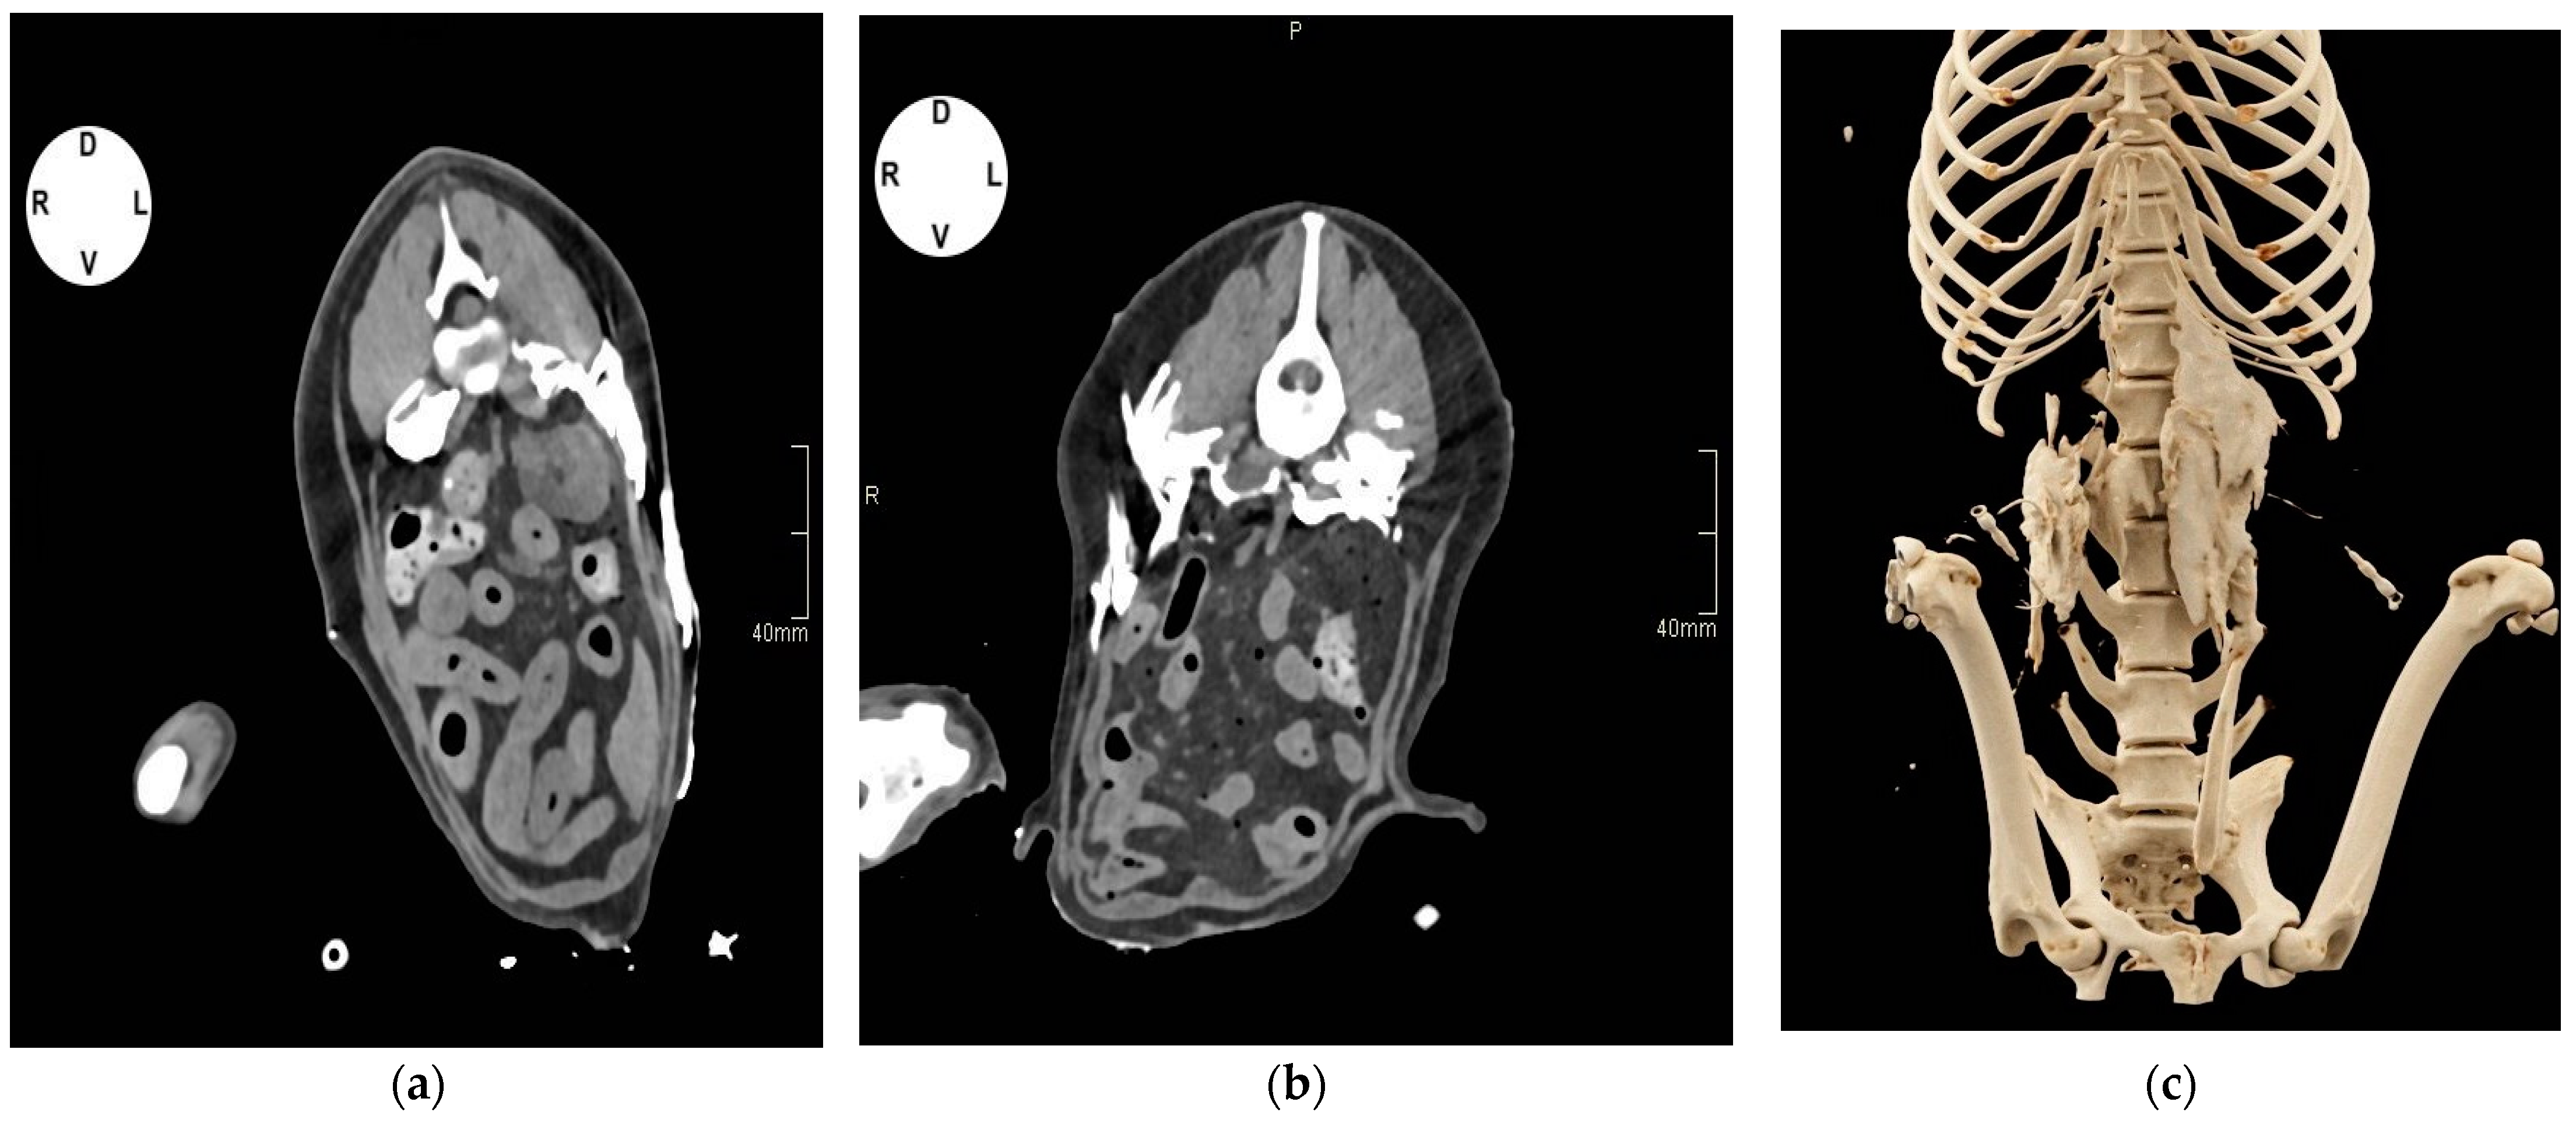

2.1.2. Tomographic Study

3.1.2. Tomographic Study